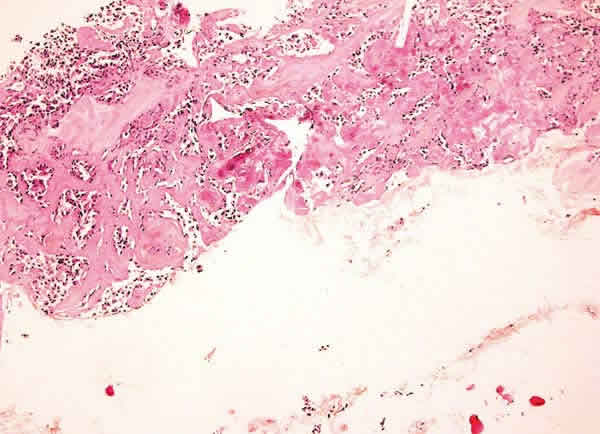

Fig. 14: Carcinoma medular. Imagen panorámica mostrando la esclerosis del estroma con abundante material eosinofílico y grupos cordonales de células con abundante artefacto (Hematoxilina-Eosina, x40).